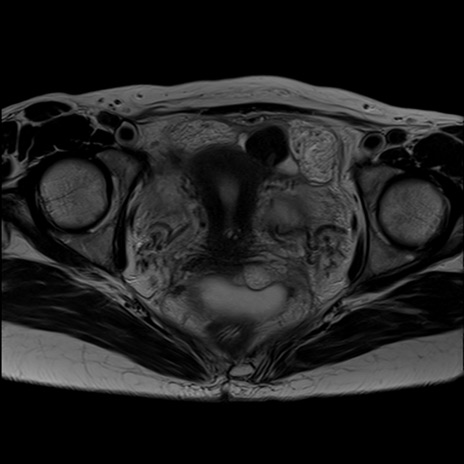

症例39 T2WI(横断像)

MRI(4日後)